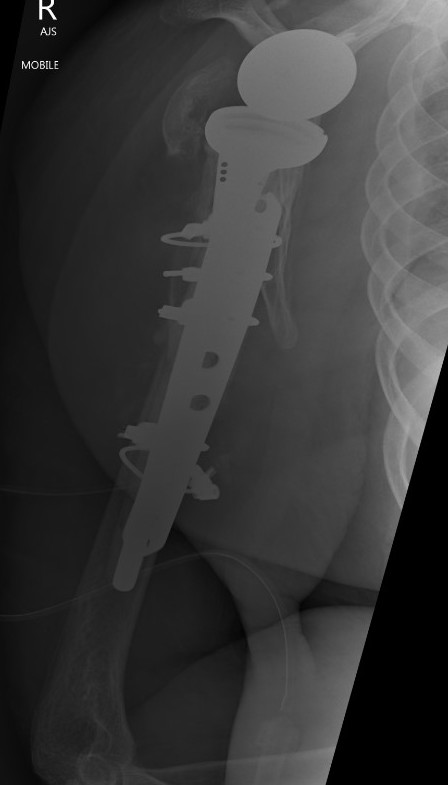

TSR Periprosthetic FractureTSR Periprosthetic Fracture

aTSA fracture 1aTSA fracture 2revTSA following fracturerevTSA for fracture